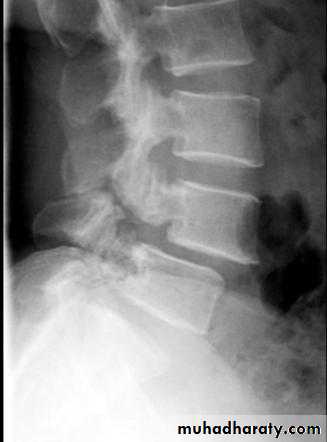

Spondylolysis and spondylolisthesis

Spondylolisthesis is a term denoting fore ward or backward movement of a vertebra relative to the vertebral segment below, typically due to spondylolysis (pars interarticularis defects) .Spondylolysis - “Spondylolysis is a defect in the pars interarticularis of the neural arch, the portion of the neural arch that connects the superior and inferior articular facet in which cause defect in the neck of scotty dog .

scotty dog sign refers to the normal appearance of the lumbar spine when seen on oblique radiographic projection. On oblique views, the posterior elements of vertebra form the figure of a Scotty dog with:

the transverse process being the nose

the pedicle forming the eye

the inferior articular facet being the front leg

the superior articular facet representing the ear

the pars interarticularis (the portion of the lamina that lies between the facets) equivalent to the neck of the dog.